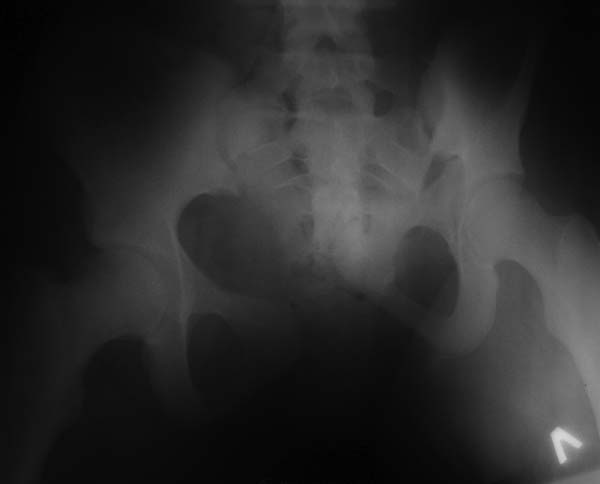

Девочка 14 лет. Кататравма (падение с высоты 4-5 этажа). Вертикально нестабильный перелом таза со смещением, разрывом лонного и левого подвздошно-крестцового сочленения, перелом крестца, открытый перелом костей голени. Ребёнок оперирован на 10-е сутки после травмы - выполнили максимально возможную репозицию на ортопедическом столе, синтез лонного сочленения реконструктивной пластиной (из имеющихся пластин - на 7 дыр - самая длинная, получилось только по 2 шурупа с каждой стороны, поэтому пришлось подстраховаться проволокой), АВФ. Задний комплекс не фиксировали ввиду отсутствия канюлированных (да и неканюлированных)шурупов должной длинны.В настоящий момент перед нами стоит вопросов:1. Обязательно ли фиксировать подвздошно-крестцовое сочленение, либо фиксации АВФ будет достаточно? Аппарат стоит достаточно стабильно, девочка при перемещениях в пределах постельного режима болевых ощущений не испытывает.2. Что делать с отломком крестца, который довольно значительно смещён кпереди? В настоящий момент никаких проблем с дефекацией у больной нет, хотя, глядя на КТ, создаётся впечатление, что отломок прямо-таки лежит на прямой кишке. Репонировать-фиксировать? Просто удалить? Вообще не трогать? Не создаст ли он в дальнейшем проблем во время родов?Хотелось бы знать мнение уважаемых коллег.Заранее спасибо.